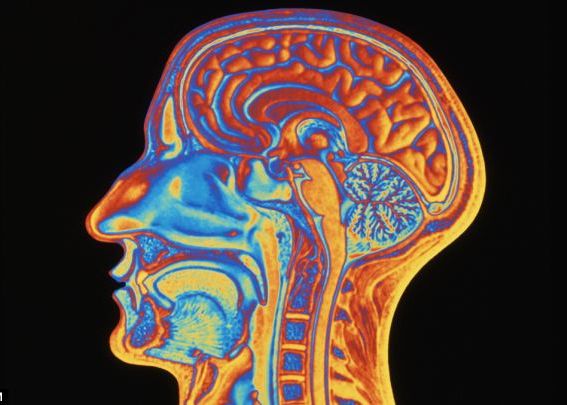

Creierul este mai rapid decat credem: vedem o imagine in doar 13 milisecunde

O echipa de oameni de stiinta din domeniul neurologiei au studiat reactia creierului uman la diverse imagini pentru a observa daca, intr-adevar, viteza de "deplasare" a imaginii este de 100 de milisecunde. Dupa mai multe teste, cercetatorii de la MIT au ajuns la concluzia ca viteza reala este de 13 milisecunde.